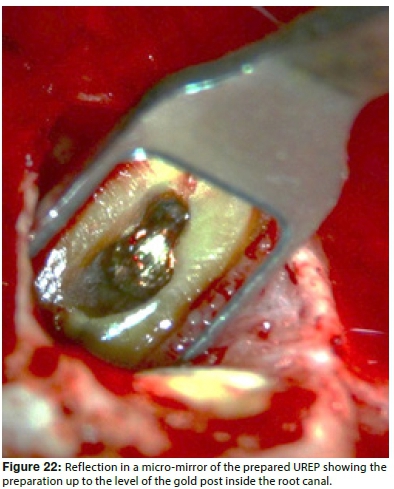

A micro-mirror was used to inspect the UREP under different magnifications, to ensure complete removal of any remaining debris in the cavity (Figure 22). Finally, the UREP was etched with 37% phosphoric acid and rinsed with water to remove the smear layer. (Ultradent) material was mixed according to the manufacturer's instructions and loaded into a skinny syringe. The mixed material was directly dispensed into the UREP and excess material was removed to the level of the resected root.